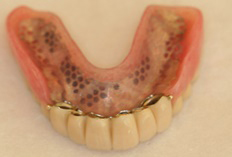

●金属床の部分入れ歯(自費)

プラスチック系の材料とコバルトクローム等の金属から構成される入れ歯です。フレームの部分が金属なので保険適応のレジン床より薄くでき、さらに、たわみにくく、精密にできているため、噛んだときに歯に負担がかかりにくい。また、義歯の下の粘膜に痛みが出にくい。修理しやすく、比較的長く使えます。